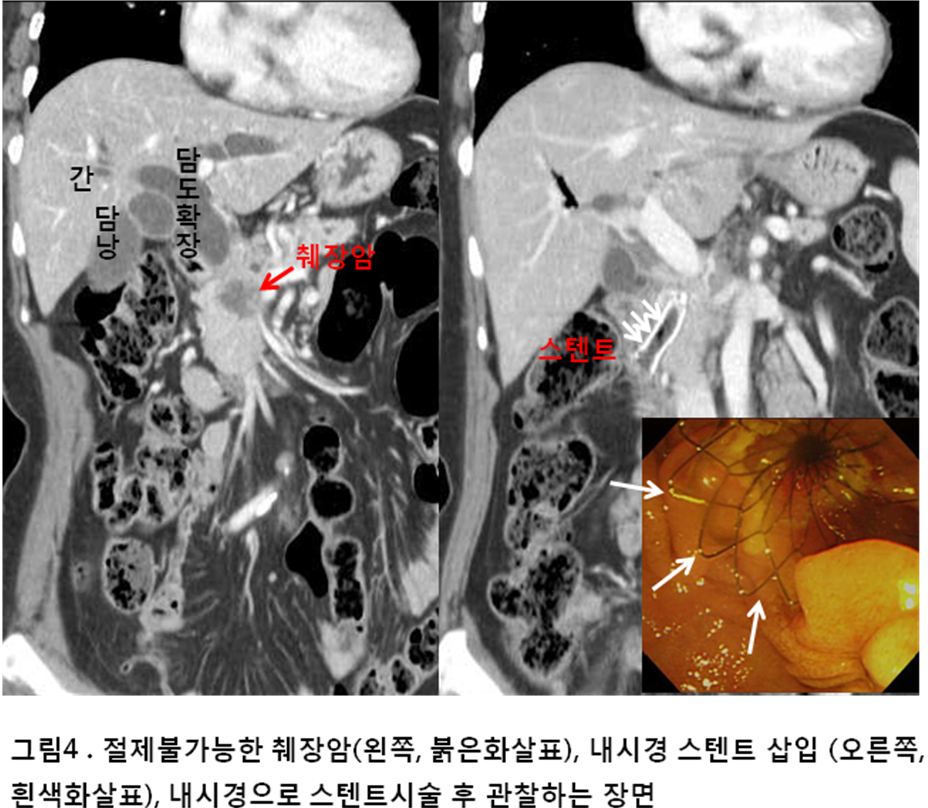

피부와 눈의 황달이 함께 나타나는 경우도 있습니다.

황달은 췌장에 종양이 생겼을 때 흔히 나타나는 증상 중 하나이므로, 즉시 전문가의 진료를 받아야 합니다.